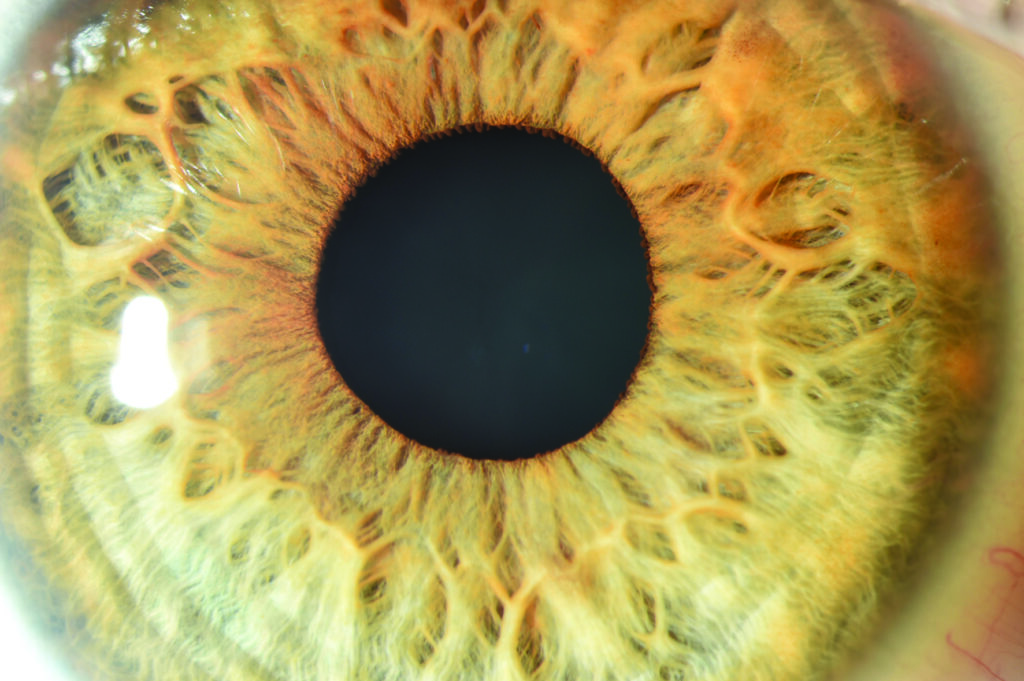

What is an anterior segment photograph?

During your eye clinic appointment you may need the outside of your eye (anterior segment) photographing to keep an accurate record of your eye condition.

This can help the doctor to diagnose, plan treatment and record your condition.